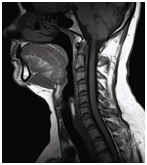

Anatómiai nyaki gerinc, láthatóvá MRI.

MRI lehetővé teszi, hogy megjelenítsék morfológiai változások: a csigolyatestek, porckorongok, gerincvelő, dura térben, az ideg gyökerek környező paravertebralis lágyrész, érrendszeri szerkezetek, amelyek a kutatási területen.

Jobb-paramedián, foraminalis porckorongsérv C6-C7.

Súlyos trauma a nyaki gerinc: a törés-zavar a C5 csigolya test, súlyos tömörítés az agytörzs, jeleivel gerincvelő-ödéma, a teljes gerinccsatorna szűkület szintjén a törés. MR kép prevertebrális vérömleny.

Mr képet spondylosis, extrudált lemez C3-C4, C4-C5, C5-C6, C6-C7.